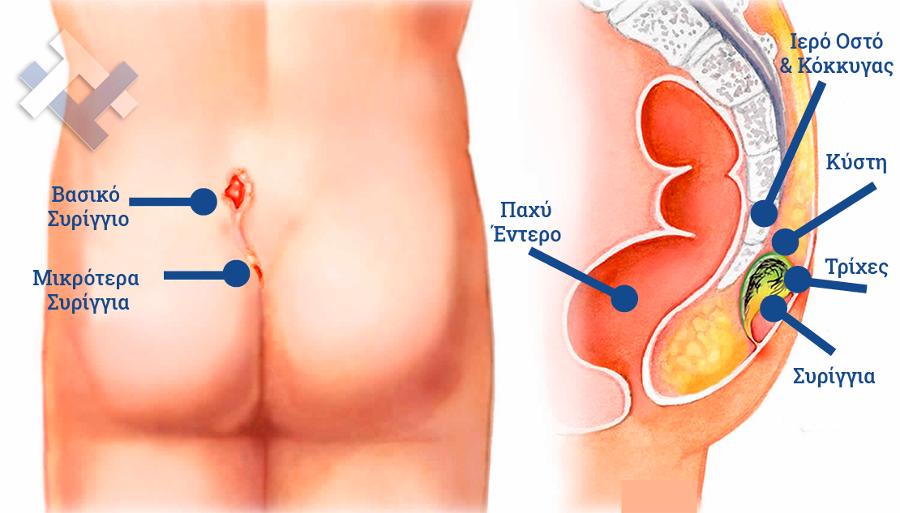

Ο Γενικός Χειρουργός Λιάγκος Γεώργιος MD PhD εκτελεί τις επεμβάσεις Λαπαροσκοπικά, Ενδοσκοπικά, Ανοιχτά Ελάχιστα Επεμβατικά και με Laser. Η θεραπεία εξατομικεύεται σε κάθε ασθενή ανάλογα με τις ανάγκες του. Αναλαμβάνει περιπτώσεις όπως κήλες και κοιλιοκήλες (αντιμετώπιση βουβωνοκήλης, αντιμετώπιση ομφαλοκήλης, θεραπεία επιγαστρικής κήλης, κήλη των αθλητών (Σύνδρομο κοιλιακών προσαγωγών), αντιμετώπιση μετεγχειρητικής κήλης, θεραπεία Μηροκήλης), πέτρες στη χοληδόχο κύστη, λαπαροσκοπική χολοκυστεκτομή, αντιμετώπιση Κύστη Κόκκυγος με λέιζερ (laser), παθήσεις πρωκτού, χειρουργική laser σύγχρονων κυκλικών ινών (αιμορροΐδες αντιμετώπιση, θεραπεία αιμορροϊδων με laser (LHP), αφαίρεση αιμορροΐδων με υπερήχους (HALL-RAR), χωρίς Χειρουργείο με ελαστικούς δακτυλίους (Τεχνική BARON-RBL), θεραπεία ραγάδας πρωκτού (Ραγάδα δακτυλίου), θεραπεία περιεδρικού συριγγίου, θεραπεία περιεδρικού αποστήματος, κονδυλώματα πρωκτού Θεραπεία, δερματικό ράκος (Skin tag) εκτομή, αντιμετώπιση Kνησμού, καρκίνος πρωκτού θεραπεία), παθήσεις Δέρματος, χειρουργική με laser CO2, αφαίρεση μορφωμάτων δέρματος - βιοψίες, αφαίρεση ελιάς (Σπίλου), σμηγματογόνος κύστης θεραπεία, αφαίρεση λιπώματος, είσφρυση όνυχος χειρουργείο, καρκίνος δέρματος θεραπεία, οξεία σκωληκοειδίτιδα, παθήσεις Λεπτού και Παχέος Εντέρου, ειλεός λεπτού εντέρου, εκκολπωμάτωση (Εκκολπωματίτιδα) σιγμοειδούς, καρκίνος παχέος εντέου, κολοστομίες, port χημειοθεραπείας κ.α.

Ο Γενικός Χειρουργός Λιάγκος Γεώργιος MD PhD εκτελεί τις επεμβάσεις Λαπαροσκοπικά, Ενδοσκοπικά, Ανοιχτά Ελάχιστα Επεμβατικά και με Laser. Η θεραπεία εξατομικεύεται σε κάθε ασθενή ανάλογα με τις ανάγκες του. Αναλαμβάνει περιπτώσεις όπως κήλες και κοιλιοκήλες (αντιμετώπιση βουβωνοκήλης, αντιμετώπιση ομφαλοκήλης, θεραπεία επιγαστρικής κήλης, κήλη των αθλητών (Σύνδρομο κοιλιακών προσαγωγών), αντιμετώπιση μετεγχειρητικής κήλης, θεραπεία Μηροκήλης), πέτρες στη χοληδόχο κύστη, λαπαροσκοπική χολοκυστεκτομή, αντιμετώπιση Κύστη Κόκκυγος με λέιζερ (laser), παθήσεις πρωκτού, χειρουργική laser σύγχρονων κυκλικών ινών (αιμορροΐδες αντιμετώπιση, θεραπεία αιμορροϊδων με laser (LHP), αφαίρεση αιμορροΐδων με υπερήχους (HALL-RAR), χωρίς Χειρουργείο με ελαστικούς δακτυλίους (Τεχνική BARON-RBL), θεραπεία ραγάδας πρωκτού (Ραγάδα δακτυλίου), θεραπεία περιεδρικού συριγγίου, θεραπεία περιεδρικού αποστήματος, κονδυλώματα πρωκτού Θεραπεία, δερματικό ράκος (Skin tag) εκτομή, αντιμετώπιση Kνησμού, καρκίνος πρωκτού θεραπεία), παθήσεις Δέρματος, χειρουργική με laser CO2, αφαίρεση μορφωμάτων δέρματος - βιοψίες, αφαίρεση ελιάς (Σπίλου), σμηγματογόνος κύστης θεραπεία, αφαίρεση λιπώματος, είσφρυση όνυχος χειρουργείο, καρκίνος δέρματος θεραπεία, οξεία σκωληκοειδίτιδα, παθήσεις Λεπτού και Παχέος Εντέρου, ειλεός λεπτού εντέρου, εκκολπωμάτωση (Εκκολπωματίτιδα) σιγμοειδούς, καρκίνος παχέος εντέου, κολοστομίες, port χημειοθεραπείας κ.α.